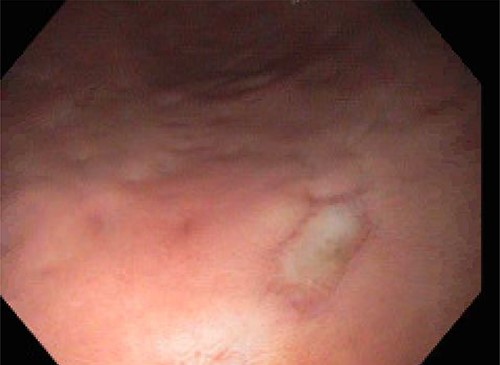

On POD 15, the patient was noted to have bloody output from the orogastric tube and esophagogastroduodenoscopy was performed. Diffuse esophageal and gastric ulcerations were noted, consistent with HSV esophagitis (Figs 1 and 2). The patient began improving clinically. Vasopressors were discontinued and patient was extubated the following morning. She was transferred out of the ICU on POD 28 with improvement of renal function and discontinuation of dialysis. Patient was discharged on POD 39.